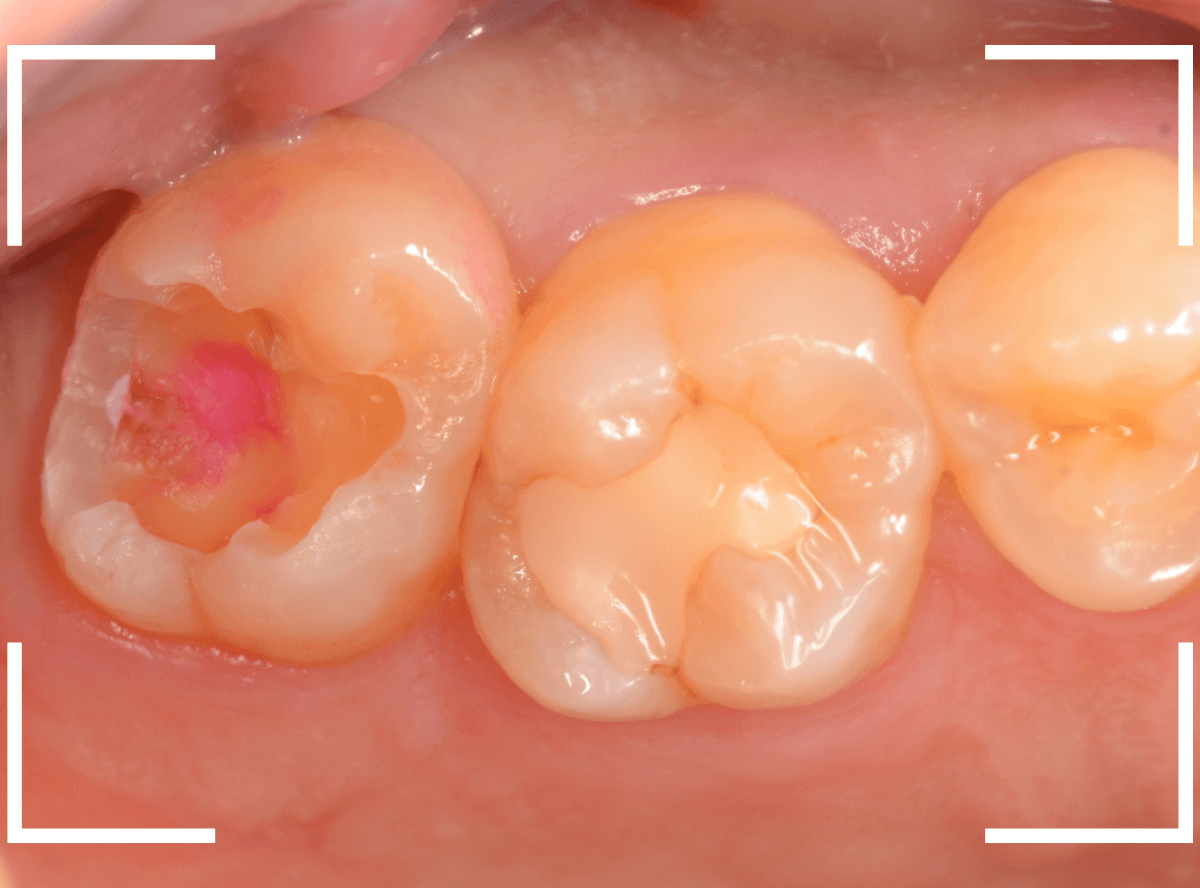

Case.10 上の一番奥の歯が、ひどい虫歯

他の歯の虫歯の治療を希望されて来院された患者さんですが、上の奥歯もひどい虫歯になっています。

レントゲン写真で確認します。

青い線が神経、赤い線が虫歯です。

予想していましたが、神経まで達してしまいそうな虫歯です。

このような状態でも、患者さんは症状なくケロッとしています。

とはいえ、いつ痛みだしてもおかしくない状況ですので、早急に治療します。

慎重に虫歯を除去します。

出来る限り歯を削る量を少なくするため、エキスカを使て、耳掃除のように手さぐりで虫歯を除去します。

虫歯に感染した歯は、このようにクッキーの食べかすのような状況になってしまいます。

虫歯をかなり除去しところで、う蝕検知液でチェックします。

赤い部分が虫歯です。

まだ虫歯が取り切れていません。

う蝕検知液で染色されないところまで、そ~っと虫歯を除去しました。

残念ながら、歯の神経が一部露出しています。

状況的には厳しいですが、神経を保護するお薬をつめて、セメントで蓋をして、痛みが出たら、神経を除去する必要がある事を説明して経過観察することになりました。

痛みがなくても、このように大きな虫歯になっている事は多くあります。

くれぐれも「痛みがある、なし」の自己判断で受診を控えるのはさけてくださいね。